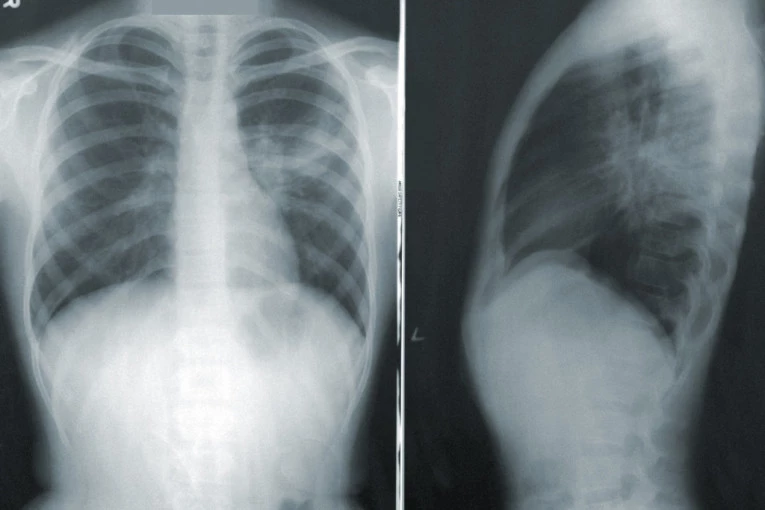

Foto: Photo by CDC on Unsplash- Toliko je mutirao ovaj virus da čovek nije siguran kako će noć da dočeka. Javlja se temperatura od 37,3 stepena sa atipičnim bolovima u zglobovima, nogama, rukama. Taj čovek odmah treba da se javi lekaru. Uradi se rendgenski snimak na kome nema ništa, ali već se iz laboratorijske analize vide klasični simptomi za početak kovida. Već za 24 časa, prvi simptomi kašlja nas navode da ponovo snimimo pluća i vidimo da li je jedno ili i drugo plućno krilo zahvaćeno, a temperatura ide preko 38. Tu enegrično moramo da pristupimo davanju terapije. Ovaj virus se mnogo brže širi i mnogo je opasniji - kaže za "Blic" dr Jerkan.

Na konsultativne preglede na Infektivnu kliniku poslato je 35 pacijenata koji su vraćeni sa terapijom, urađeno je 158 snimaka pluća sa 52 nalaza na plućima. Od 1.018 pacijenata je uzeta laboratorija, urađeno je 379 PCR testova, od kojih 80 pozitivnih, i 607 antigenskih testova, od kojih je 270 bilo pozitivnih.